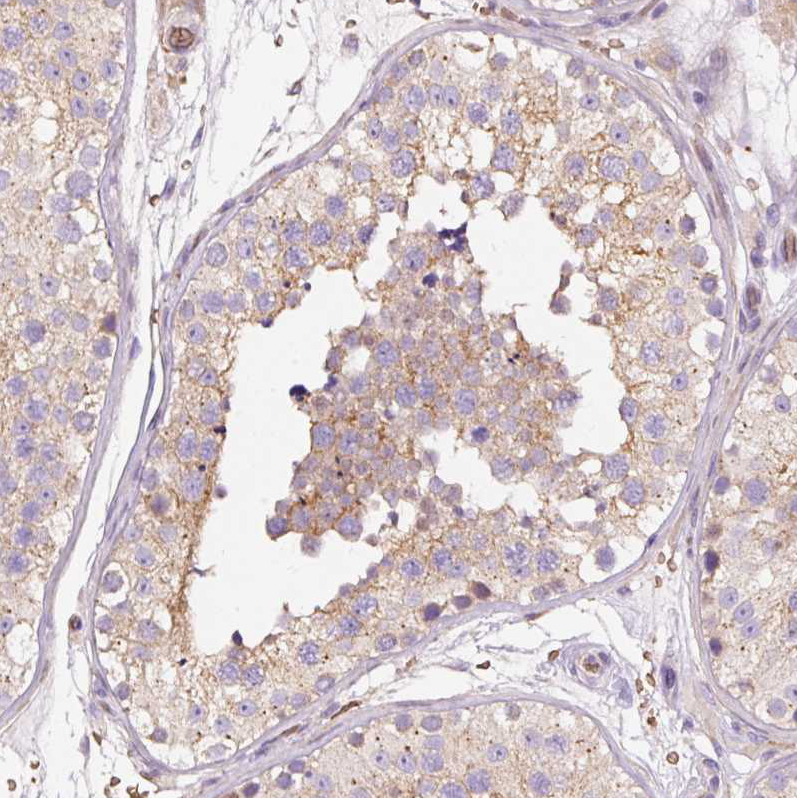

Immunohistochemical staining of human testis shows weak cytoplasmic positivity in cells in seminiferous ducts.